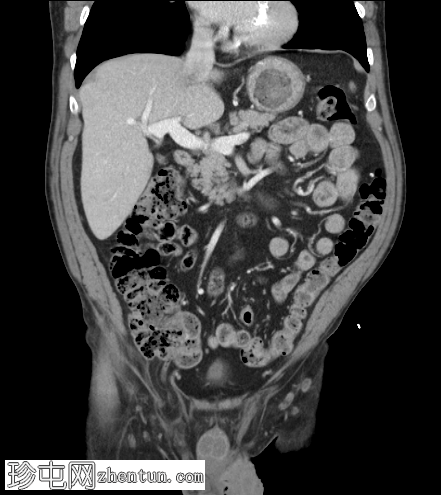

冠状C+门静脉期

右侧腹股沟斜疝,包含网膜脂肪,延伸至阴囊颈。疝囊内包含正常阑尾(轴向、冠状),符合Amyand疝。

双侧精索脂肪增多症。

包含阑尾的腹股沟疝称为Amyand疝,无论阑尾是正常的还是发炎的(阑尾炎)。